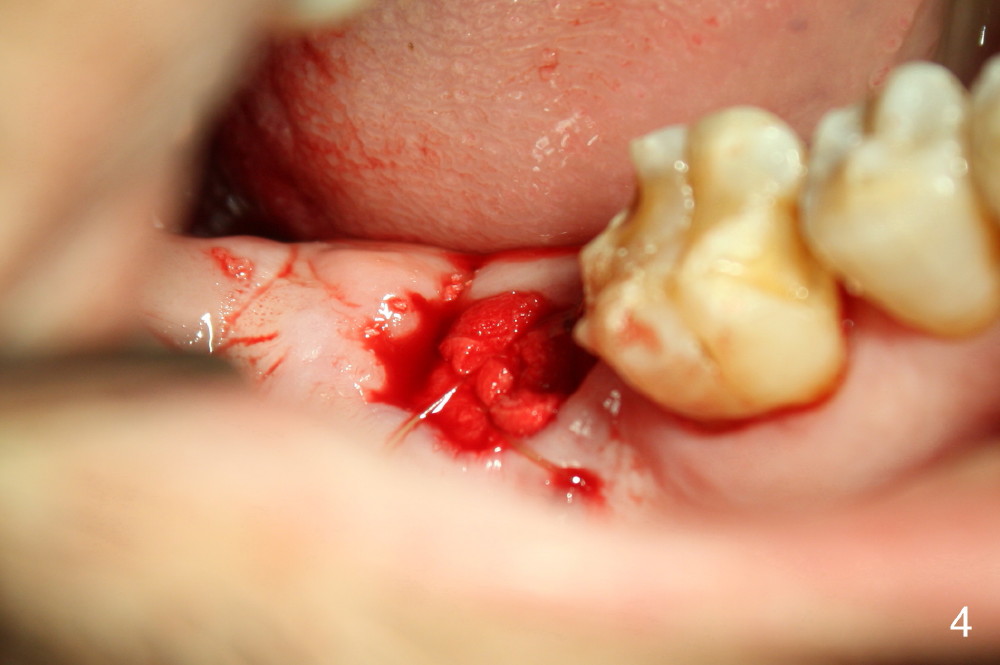

A 52-year-old man (heavy smoker) presents to office without schedule.  He has severe pain at #31 and wants extraction immediately (Fig.1,2).  He likes the idea of immediate implant, but we do not have time for it that day.  Therefore the tooth is extracted (Fig.3).  The socket is single.  After debridement, bone graft (Fig.5 *) and collagen membrane (Fig.4) are placed.

The patient will return for implant placement 2.5 months post extraction.  He must be a gagger, because PAs in Fig.2,5 are taken with sensor 1.  The Inferior Alveolar Nerve is out of view.  It appears that he is too busy to have CBCT taken in the other office.